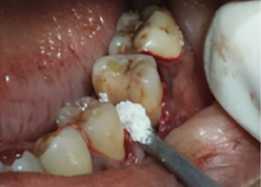

Placement of PRF Membrane